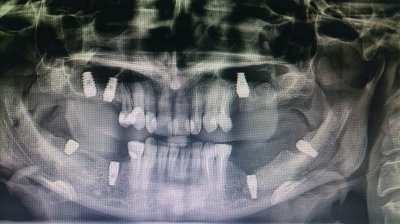

это прочистка каналов, если не ошибаюсь? Недавно прошел это. Вон на снимке видно, как накосячили

Иллюстрация к комментарию

6 "пересверлен"+кариес корня. 7 - инструмент в канале, который не достанешь при всем желании и похоже на перфорацию корня,

Ну по поводу 6 согласна.а вот за седьмой можно попробовать побороться.каналонаполнители достаточно легко вытаскиваются. Если удастся пройти канал, то все будет гуд

по поводу каналонаполнителя тоже не согласна,под микроскопом вполне можно вытащить!